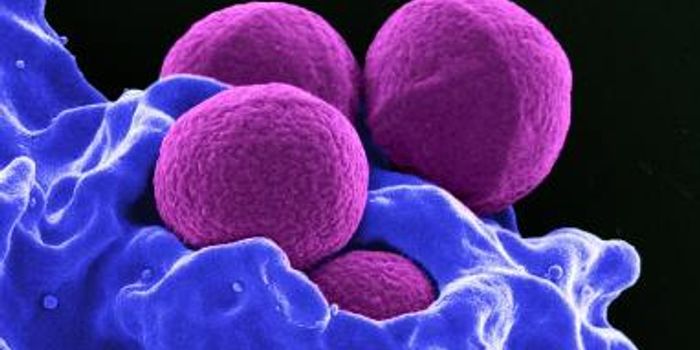

OCT 30, 2015MicrobiologyStaphylococcus aureus is notorious for forming biofilms on indwelling medical devices (things like urinary and vascular ...